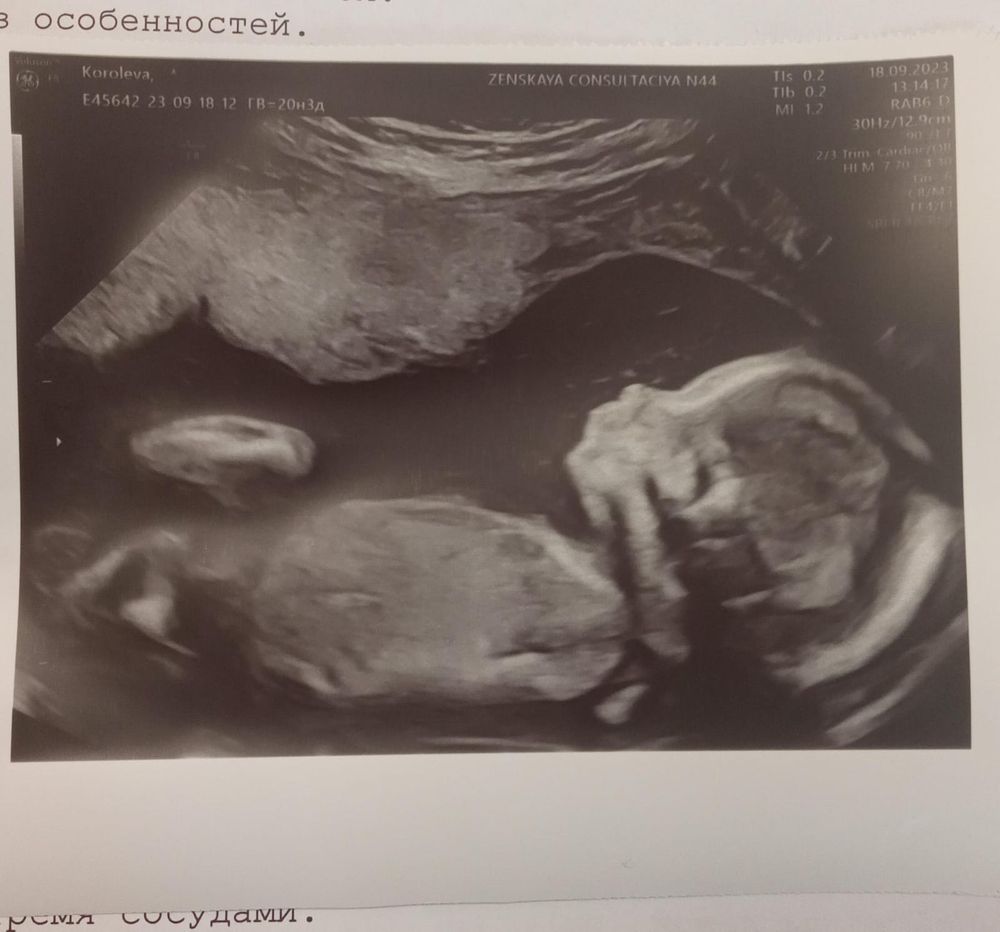

На днях прошла второй скрининг. Даже ещё не верится, что я нахожусь в интересном положении , хотя живот уже достаточно большой, и ощущаются такие долгожданные пиночки . Правда , снаружи они ещё не ощутимы, но изнутри очень даже. За 2 дня до скрининга меня настигла паническая атака по поводу моей шейки, что то кололо, тянуло, распирало , а я накручивала себя и представляла самые плохие варианты. В итоге, эти 2 дня просто лежала практически не вставая, клала подушечку под попу и подушку побольше под ноги. В итоге, по УЗИ, шейка 28мм, зев закрыт, всё остальное в норме, подтвердили девочку. Сделали фото, если сравнивать с фото с первого скрининга, то как будто бы 2 разных ребенка)